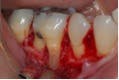

In primary endodontic disease, an acute exacerbation of a chronic apical lesion that has been caused by a necrotic pulp may result in temporary loss of alveolar bone, which can provide an avenue of drainage through the PDL into the gingival sulcus. Normally, this drainage is either not present or is seen as a sinus tract appearing in the attached gingiva. Radiographically, this condition may present as a periodontal problem, demonstrating severe bone loss. A so-called “pseudopocket” may form, with probing depths to or even past the apex of a root. The furcation of a multi-rooted tooth may also be seen to be involved (Figure 1). Diagnostically, pulp testing must be performed, specifically with thermal stimulation. A “no response” is indicative of a non-vital pulp and is diagnostic for endodontic involvement. After establishing the reason the pulp became non-vital and ruling out vertical crown and/or root fracture, conventional root canal therapy is performed (Figure 2). Removal of bacteria, bacterial by-products, and other immunogenic materials from the root canal system, followed by proper obturation, allows surrounding bone to recover and heal normally, with resolution of all periodontal pockets (Figure 3). Endodontic disease may be thought of as an “acute” process as opposed to a “chronic” process, and once the primary cause of the infection (the non-vital pulp) has been addressed and resolved, normal healing ensues.